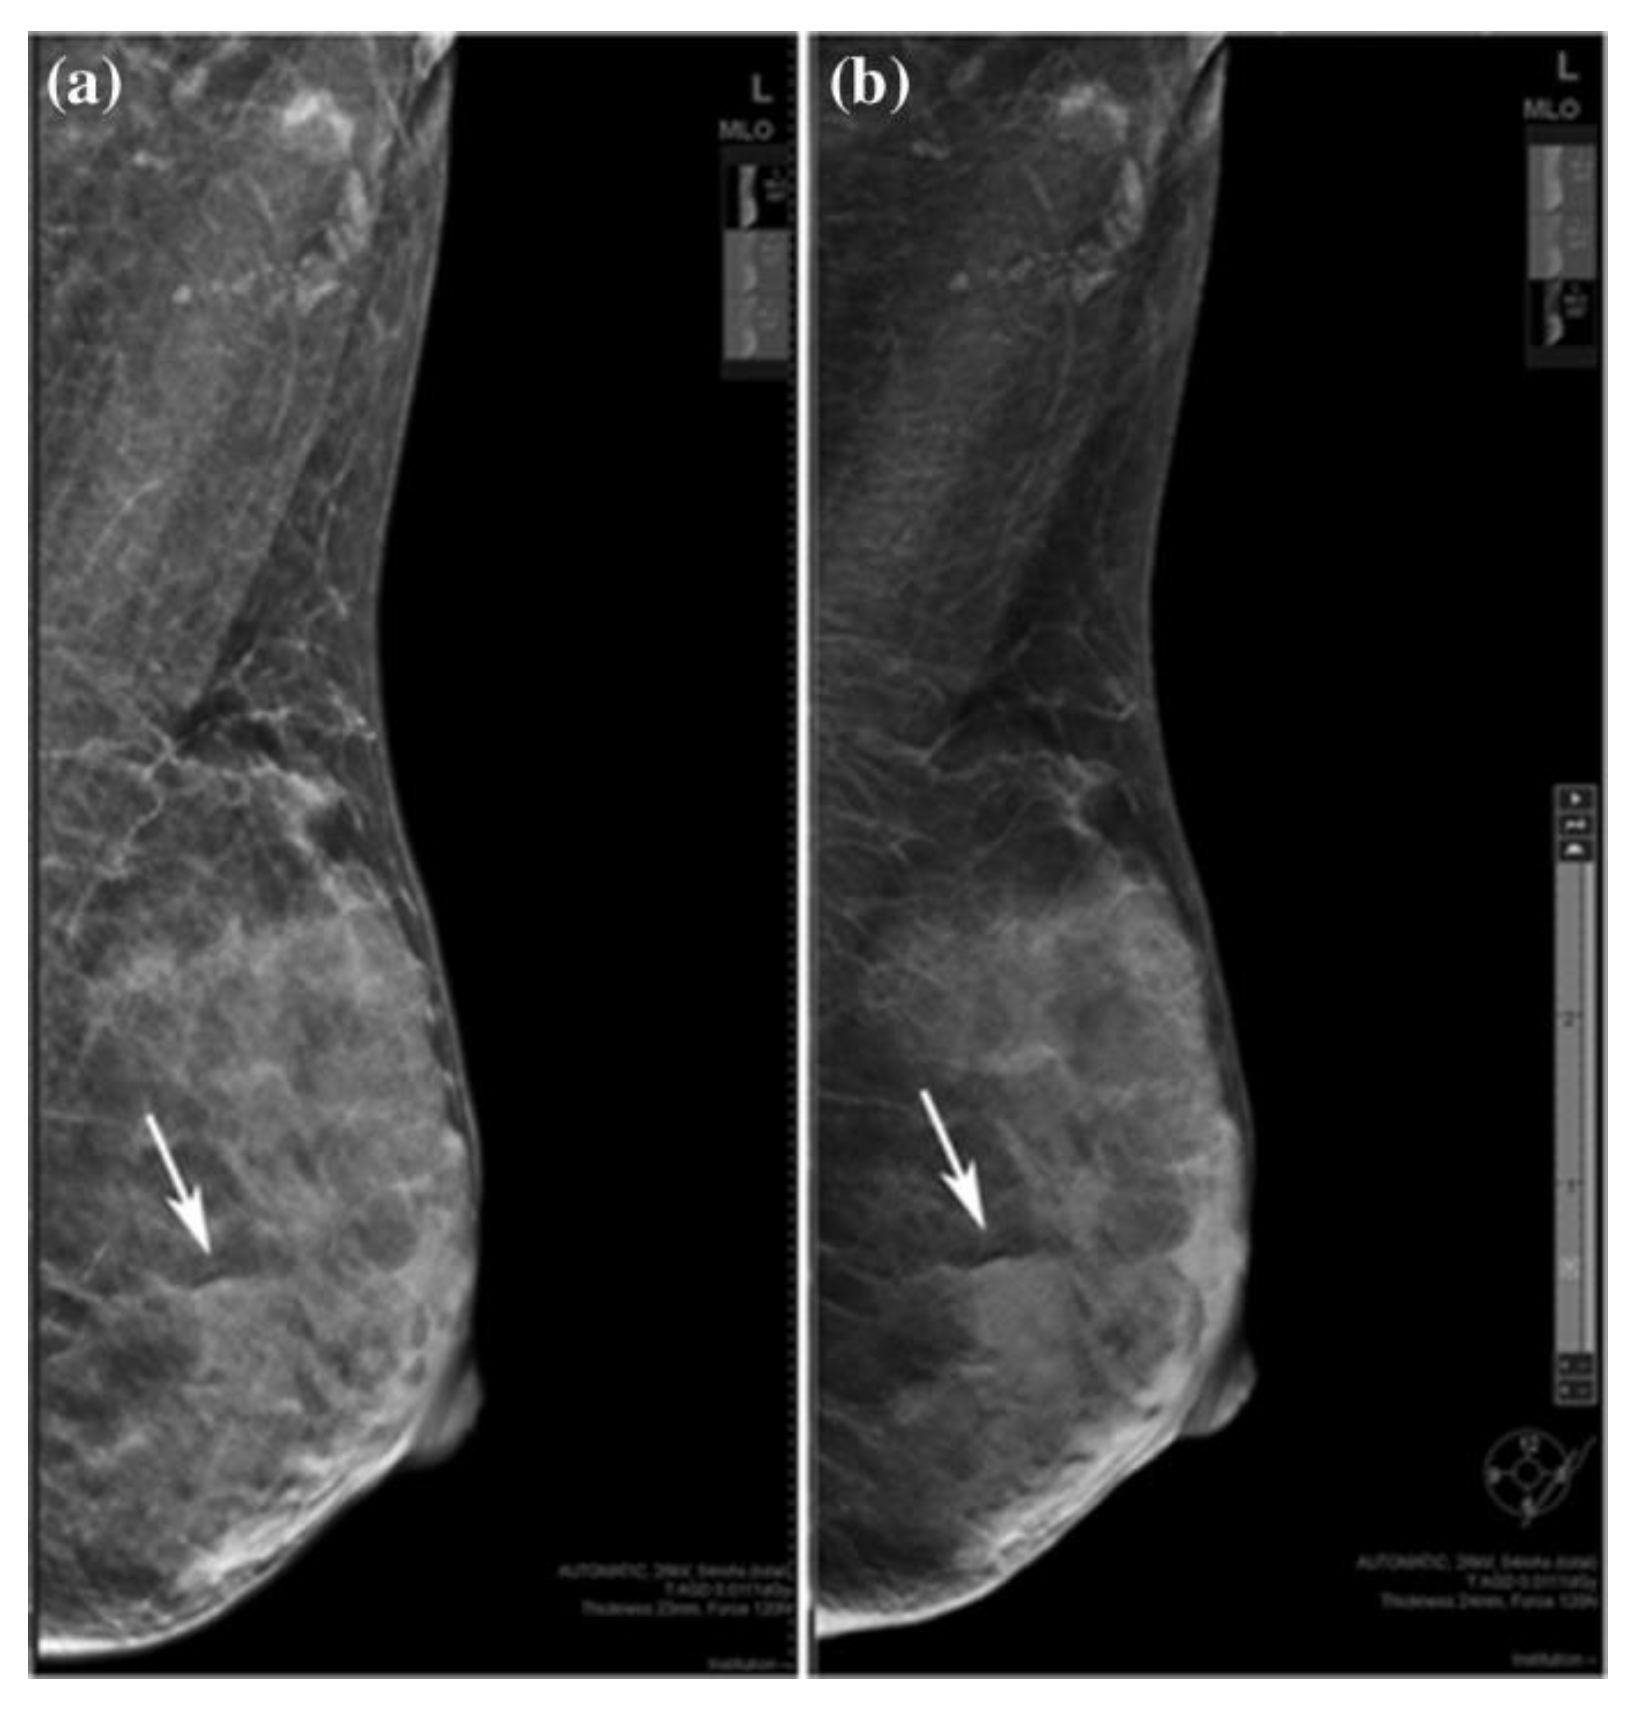

2.2. Digital breast tomosynthesis (DBT)

- Østerås, B.H.; Martinsen, A.C.T.; Gullien, R.; Skaane, P. Digital Mammography versus Breast Tomosynthesis: Impact of Breast Density on Diagnostic Performance in Population-based Screening. Radiology 2019, 293, 60–68. [Google Scholar] [CrossRef]

- Lee, S.H.; Jang, M.J.; Kim, S.M.; Yun, B.L.; Rim, J.; Chang, J.M.; Kim, B.; Choi, H.Y. Factors affecting breast cancer detectability on digital breast tomosynthesis and two-dimensional digital mammography in patients with dense breasts. Korean Journal of Radiology 2019, 20, 58–68. [Google Scholar] [CrossRef] [PubMed]

- Yi, A.; Chang, J.M.; Shin, S.U.; Chu, A.J.; Cho, N.; Noh, D.-Y.; Moon, W.K. Detection of noncalcified breast cancer in patients with extremely dense breasts using digital breast tomosynthesis compared with full-field digital mammography. The British Journal of Radiology 2019, 92, 20180101. [Google Scholar] [CrossRef] [PubMed]